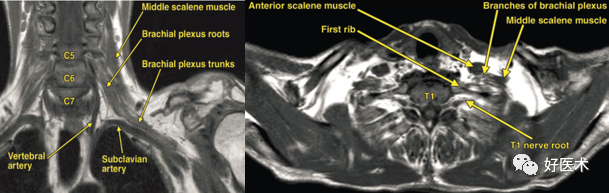

解剖结构 胸廓出口上界为锁骨,下界为第一肋骨,前方为肋锁韧带,后方为中斜角肌。上述肋锁间隙又被前斜角肌分为前、后两个部分。锁骨下静脉位于前斜角肌的前方与锁骨下肌之间;锁骨下动脉及臂丛神经则位于前斜角肌后方与中斜角肌之间。 臂丛血管神经经肋锁间隙到达腋窝三角底部,任何可使胸廓出口通道狭窄的原因均会导致神经血管压迫而产生症状。 前斜角肌起自第3~6颈椎横突的前结节,肌纤维向前外下走行,止于第1肋骨的前端上缘锁骨下动脉沟前方的前斜角肌结结节。 中斜角肌多数起自所有颈椎横突后结节,少数起自第2~7、3~7或3~7颈椎横突后结节,向外下止于第1肋骨上面锁骨下动脉沟的后方或外后方。 前、中斜角肌与第1肋骨构成的一三角形间隙,称为斜角肌间隙。 支配上肢的血管神经有臂丛神经及锁骨下动、静脉。 锁骨下动脉自主动脉弓发出后,呈弓形跨越第1肋骨,穿过斜角肌间隙,进入肋锁间隙。锁骨下静脉并不通过斜角肌间隙,而是自前斜角肌的前方越过,注入颈静脉。 臂丛神经由C5至T1神经根前支组成,各神经根出椎间孔后向外下走行,于锁骨下动脉的后上方穿过斜角肌间隙。 C5、C6神经根组成臂丛神经的上干,C7神经根单独组成中干,C8、Tl神经根组成臂丛神经的下干,其中下干直接跨越第1肋骨,各干分为前、后两股共同走行于肋锁间隙内,向外下通过此间隙后,进入胸小肌后面的胸小肌后间隙,再进入腋部。在神经及血管束的周围,有纤维结缔组织形成的神经血管鞘。 臂丛神经的上述行程中,在以下部位最易受压: ①斜角肌间隙 ②肋锁间隙 ③胸小肌后间隙 上述解剖部位的任何先天性或后天因素所造成的异常,均可直接或间接地压迫锁骨下血管及臂丛神经,产生临床症状。 病因病理 (一)病因 1.先天性因素 先天性的解剖结构异常包括骨性异常及软组织的异常。 常见的骨性异常有: 颈肋 第7颈椎横突过长 锁骨或第1肋骨的上移使肋锁间隙狭窄 软组织异常: 由于前中斜角肌的肥厚; 斜角肌先天性束带,多在前斜角肌与第 l 肋骨之间形成束带,压迫血管神经; 斜角肌挛缩,斜角肌间隙变小; 胸小肌的止点异常以及其他部位先天性的异常纤维束带压迫等 。 2.后天性因素 包括在上述解剖部位的肌肉组织增生及萎缩而导致肌肉力量失衡,解剖位置改变,牵拉及压迫血管神经束; 长颈及肩胛带下垂的人群易发生胸廓出口综合征; 创伤在胸廓出口综合征的发生中亦有一定的作用,锁骨及肋骨骨折不仅可直接损伤锁骨下血管及臂丛神经,而且可因骨折畸形愈合、异常的骨痂生长、局部瘢痕组织增生以及肌肉组织损伤后出血水肿.纤维化,压迫血管神经束; 血管损伤产生的假性动脉瘤或胸廓出口处发生的肿瘤也可直接压迫臂丛神经; 臂丛神经先天性变异、颈肩部的急性牵拉伤、长期的姿势不良、颈肩部的肌肉失衡、巨乳、肥胖等也是引起胸廓出口综合征(TOS)不可忽视的因素。